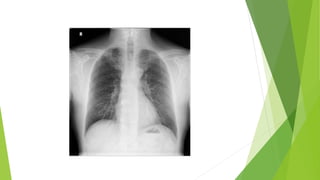

 Chest x-ray.

 Pulse Oximetry. Chest x-ray.  CT Scan.  Bronchoscopy  Thoracoscopy  Percutaneous aspiration/biopsy  Open lung biopsy